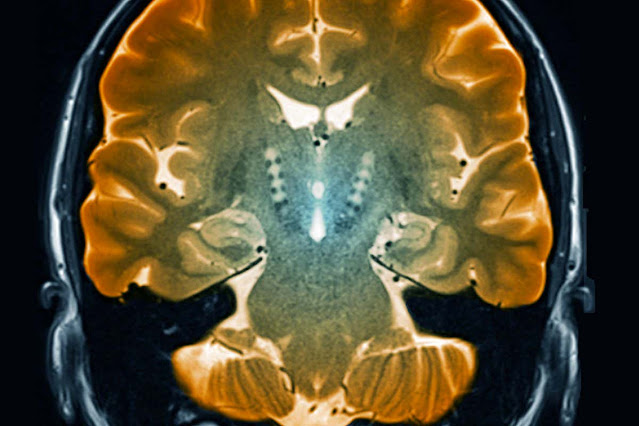

Loss of dopaminergic neurons in the part of the midbrain called the

substantia nigra is a pathological hallmark of Parkinson's disease. While

Measuring the levels of gene activity in single cells, the team identified

10 distinct subtypes of dopamine-producing neurons in the substantia nigra,

each distinguishable by their gene activity profiles.

On closer inspection, they found that molecular processes linked to cell

death in other neurodegenerative diseases were amped up in this particular

group of dopaminergic neurons, and they pinpointed exactly where the cells

usually reside: in the underside of the substantia nigra pars compacta.